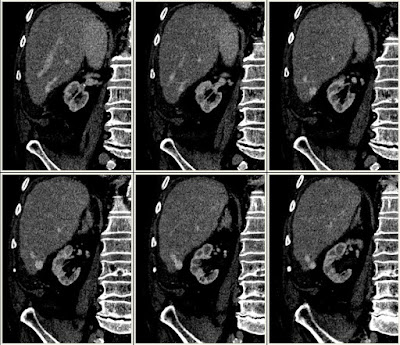

Szerző: admin | máj 10, 2011 | Renal tumor, Thrombosis, Vascular

a tumorthrombus cranialis része nem érintkezik a vénafallal (lebegő)8114092011.05.06.